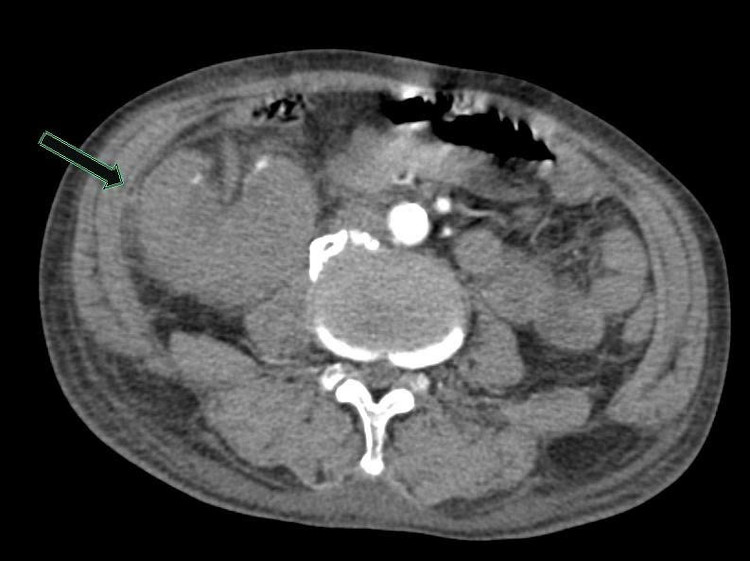

Các bác sĩ đã nhanh chóng thực hiện các cận lâm sàng cần thiết. Kết quả chụp CT-Scanner ổ bụng ghi nhận viêm thận – bể thận phải, thận phải lạc chỗ và giãn đài bể thận trái.

Hình ảnh chụp Cắt lớp vi tính có tiêm thuốc cản quang: Thận phải lạc chỗ, nhu mô thận phải ngấm thải thuốc kém hơn thận trái, bể thận xoay ngoài, nhu mô thận có hình ảnh các ổ không ngấm thuốc (quan sát rõ ở các thì tĩnh mạch và thì muộn) - Ảnh BVCC